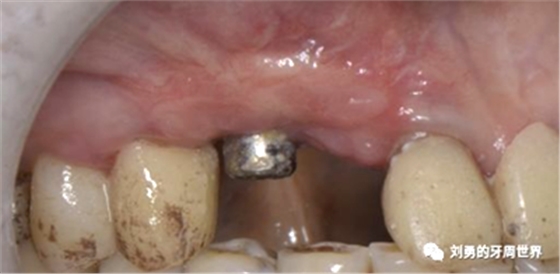

下面這個是我使用國產(chǎn)的替代品的病例:

上圖中,種植體唇側缺乏附著齦,從上腭取瓣,常規(guī)做法:取長而寬的齦瓣,這樣供區(qū)面積大,術后疼痛重。

為了減少痛感,從雙側上腭取多條長而窄的齦瓣進行移植,這樣每個供區(qū)的傷口都比較窄,可以減少術后的痛感。

可見右上前牙植體頰側無附著齦

為了減少取瓣大小,從上腭取厚一點的齦瓣,然后用刀片平行于表皮表面將齦瓣片切成兩個厚度一致的齦瓣,然后進行移植,這樣切成的兩個齦瓣一個有表皮,一個沒有表皮是單純的結締組織。如此的片切可以使齦瓣變成雙倍的大小使用,減少了供區(qū)的取瓣面積。